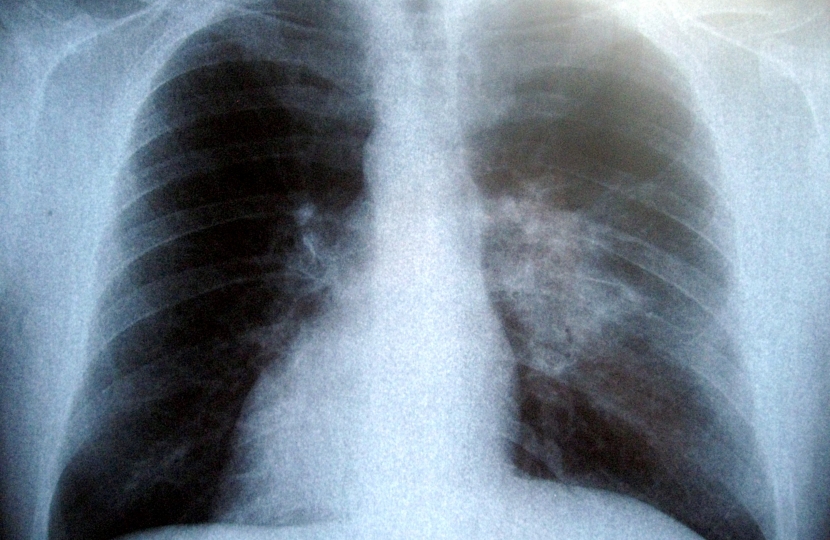

The test allows people to check their health through 10 simple questions, based around the Medical Research Council breathlessness scale. The aim is to reassure people who don't have a problem and guide those with significant breathlessness to make an appointment with their GP.

“70% of those taking our simple online test were found to have concerning breathlessness, which meant they were supported to get help from their GP. But crucially, the 30% who had their minds put to rest did so without having to visit a doctor, reducing unnecessary strain on our health service.